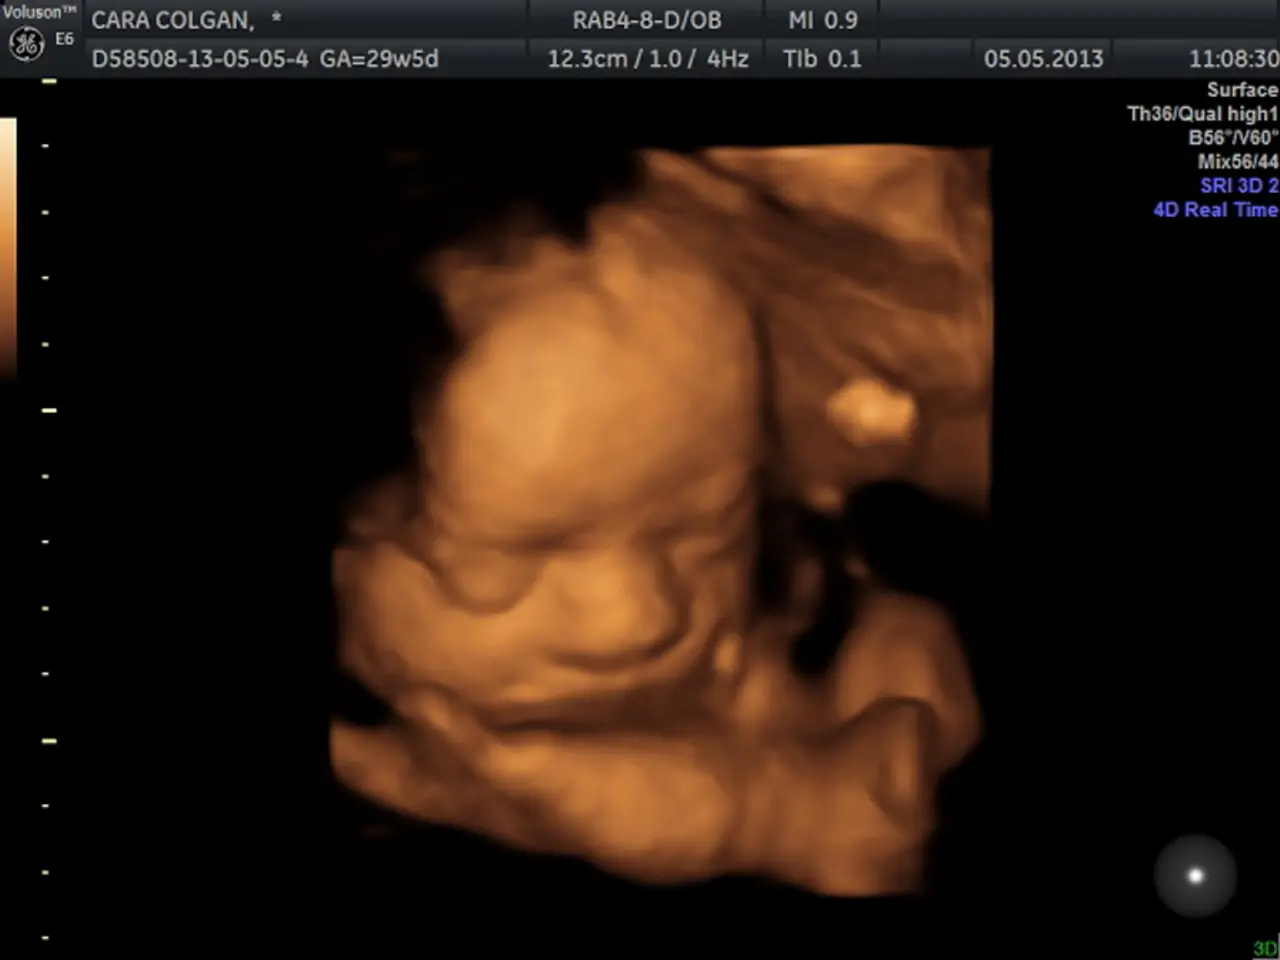

The study, conducted by the Mental Illness Neurobiology group of the mixed research centre of CSIC and the University Miguel Hernández, analysed several human brains of 20-week-old fetuses anonymously donated after a spontaneous abortion in 2020.